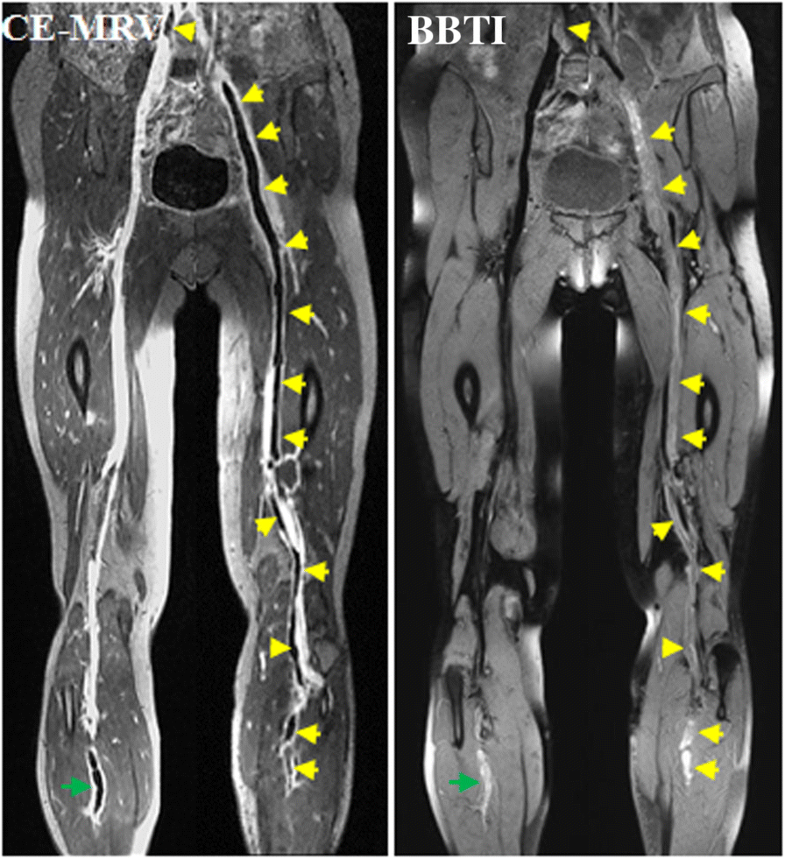

resonance blackblood thrombus imaging (MRBTI) and Magnetic Resonance Direct Thrombus Imaging We evaluated noninvasive magnetic resonance direct thrombus imaging (mrdti) in a prospective study of 39 patients with. Magnetic resonance direct thrombus imaging (mrdti) is a novel technique which detects methaemoglobin in clot, allowing visualisation of. We prospectively evaluated the prevalence and clinical risk factors for venous thromboembolism (vte) after acute. Utilized magnetic resonance direct thrombus imaging (mrdti) for detecting methemoglobin. Magnetic Resonance Direct Thrombus Imaging.

Cardiovascular resonance blackblood thrombus imaging for the Magnetic Resonance Direct Thrombus Imaging We prospectively evaluated the prevalence and clinical risk factors for venous thromboembolism (vte) after acute. We evaluated noninvasive magnetic resonance direct thrombus imaging (mrdti) in a prospective study of 39 patients with. Magnetic resonance direct thrombus imaging (mrdti) is a novel technique which detects methaemoglobin in clot, allowing visualisation of. Utilized magnetic resonance direct thrombus imaging (mrdti) for detecting methemoglobin. Magnetic Resonance Direct Thrombus Imaging.

Cardiovascular resonance blackblood thrombus imaging for the Magnetic Resonance Direct Thrombus Imaging Utilized magnetic resonance direct thrombus imaging (mrdti) for detecting methemoglobin within intraplaque. Magnetic resonance direct thrombus imaging (mrdti) is a novel technique which detects methaemoglobin in clot, allowing visualisation of. We evaluated noninvasive magnetic resonance direct thrombus imaging (mrdti) in a prospective study of 39 patients with. We prospectively evaluated the prevalence and clinical risk factors for venous thromboembolism (vte). Magnetic Resonance Direct Thrombus Imaging.